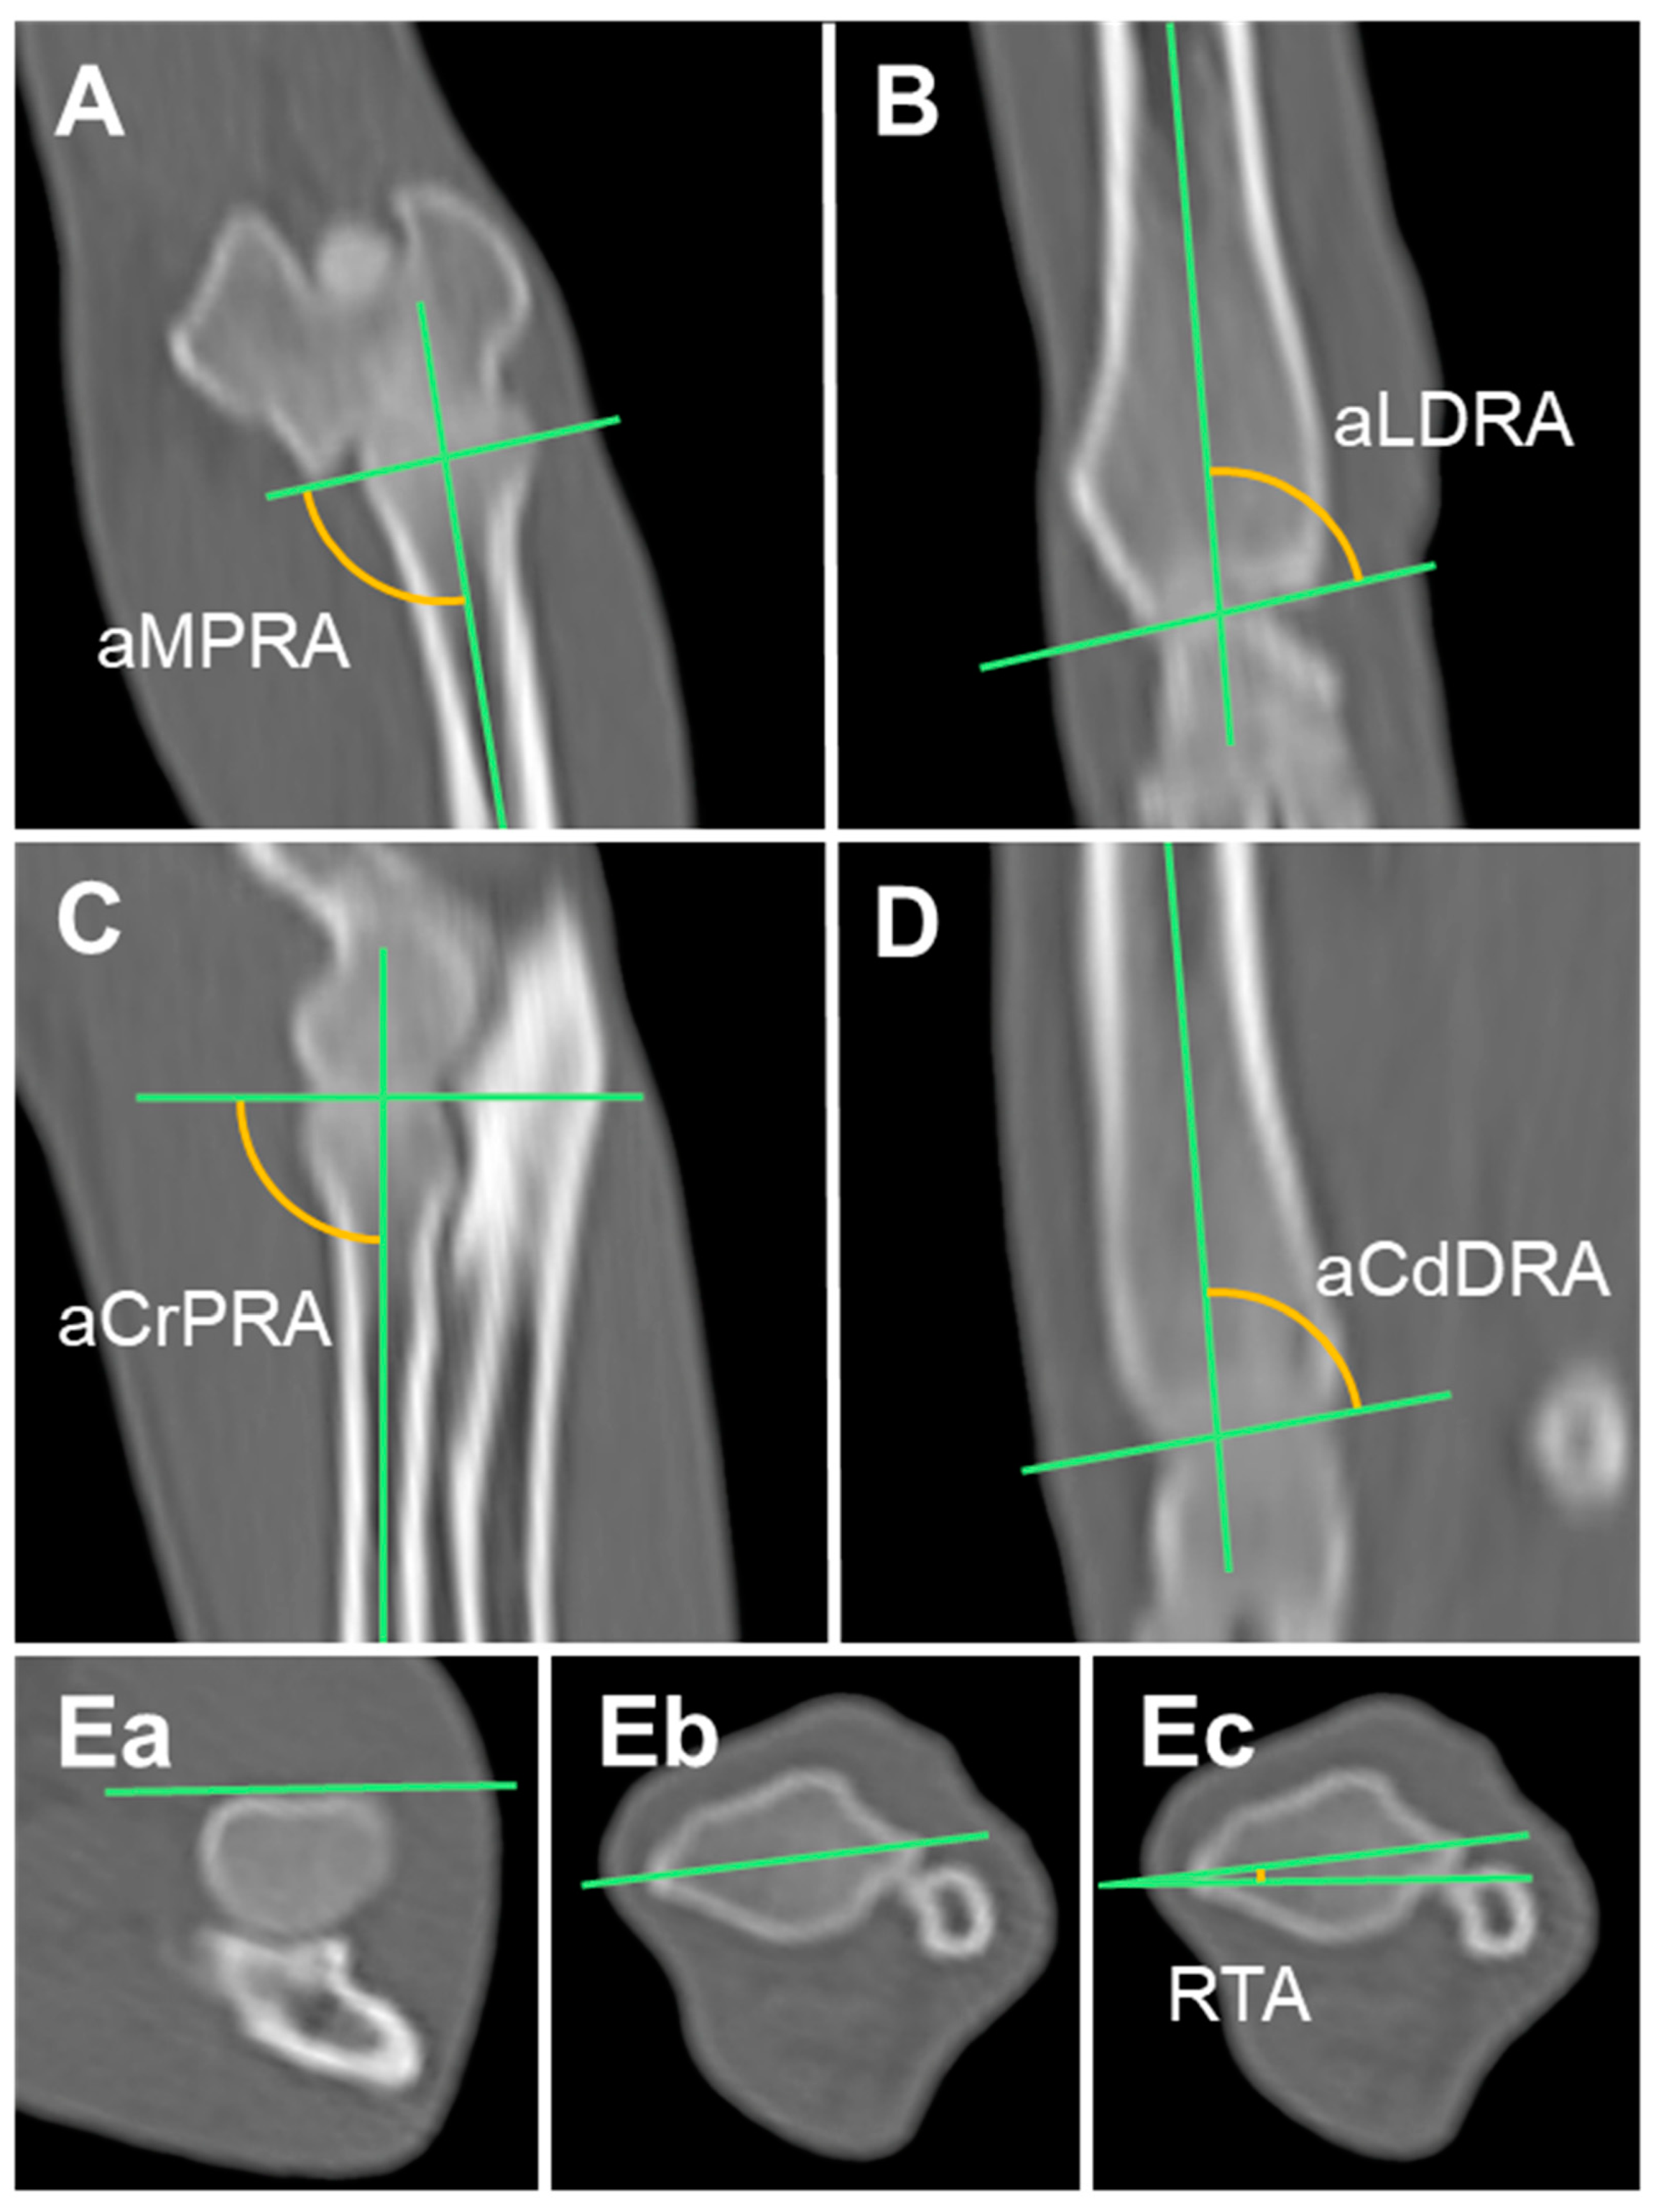

2.3.4. Anatomical Medial Proximal Radial Angle (aMPRA) and Anatomical Lateral Distal Radial Angle (aLDRA)

2.3.5. Anatomical Cranial Proximal Radial Angle (aCrPRA) and Anatomical Caudal Distal Radial Angle (aCdDRA)

2.3.6. Radial Torsional Angle (RTA)